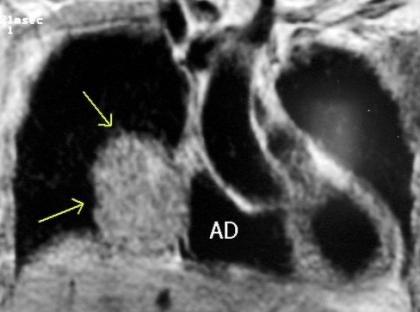

“Draped aorta”.

Indica rotura aórtica reciente. Se manifiesta por una pared aórtica posterior o el contacto con el borde lateral vertebral borrados por la hemorragia.

A. Yudin, Metaphorical

Rotura aneurisma de Aorta descendente.